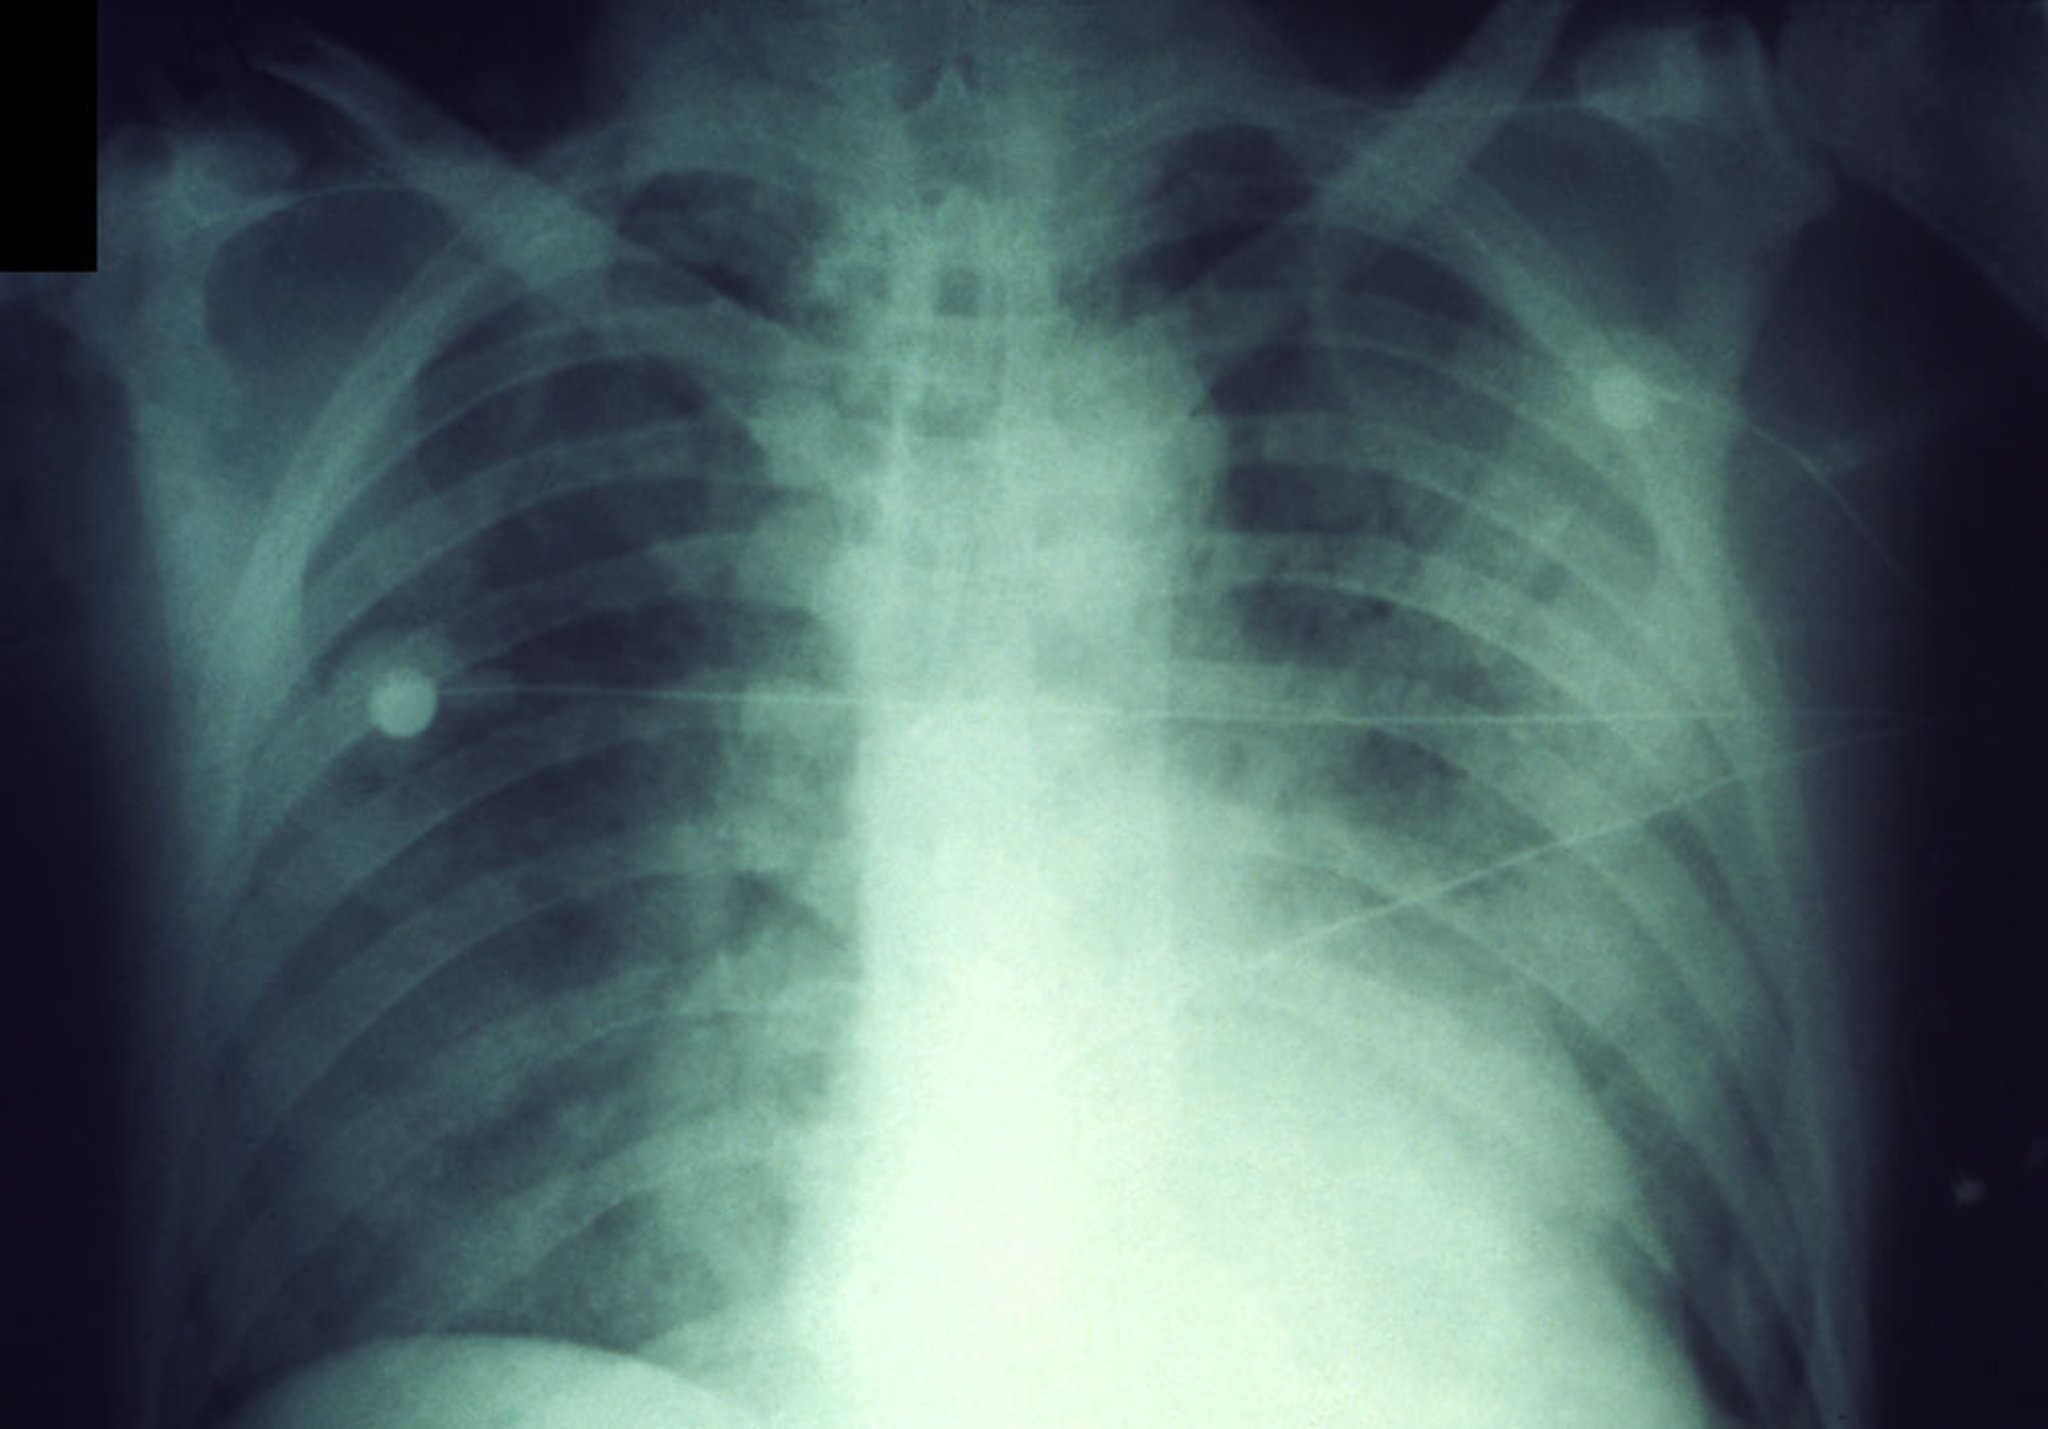

肺ペスト

この胸部X線写真には,肺ペストの急速に進行する浸潤影が写っている。

CDC/Dr. Jack Poland